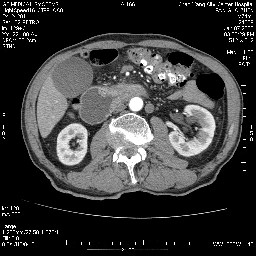

考虑来源于十二指肠水平段的恶性占位,侵及周围组织,特别是胰腺,可见区域淋巴结肿大,左侧下腔静脉畸形。

考虑来源于十二指肠水平段的恶性占位,侵及周围组织,特别是胰腺,可见区域淋巴结肿大,左侧下腔静脉畸形。支持

十二指肠水平段腔内占位伴梗阻,中等度较为均匀的强化,洗脱慢,区域淋巴结显示增多,符合腺癌表现。下腔静脉变异。

病变主要位于钩突(癌)。如是壶腹部,肝内外胆管扩张明显。

十二指肠降段扩张,水平段狭窄成鼠尾状,肠壁明显增厚,胰腺勾突增大成不均匀强化,其内可见低密度区,胆囊增大,1十二指肠水平段腺癌侵犯胰腺勾突可能大,2胰腺癌侵犯十二指肠(只有胆囊增大没有肝内外胆管扩张不好解释)代除外.

十二指肠降段扩张,水平段狭窄成鼠尾状,肠壁明显增厚,胰腺勾突增大成不均匀强化,其内可见低密度区,胆囊增大,1十二指肠水平段腺癌侵犯胰腺勾突可能大,2胰腺癌侵犯十二指肠 。